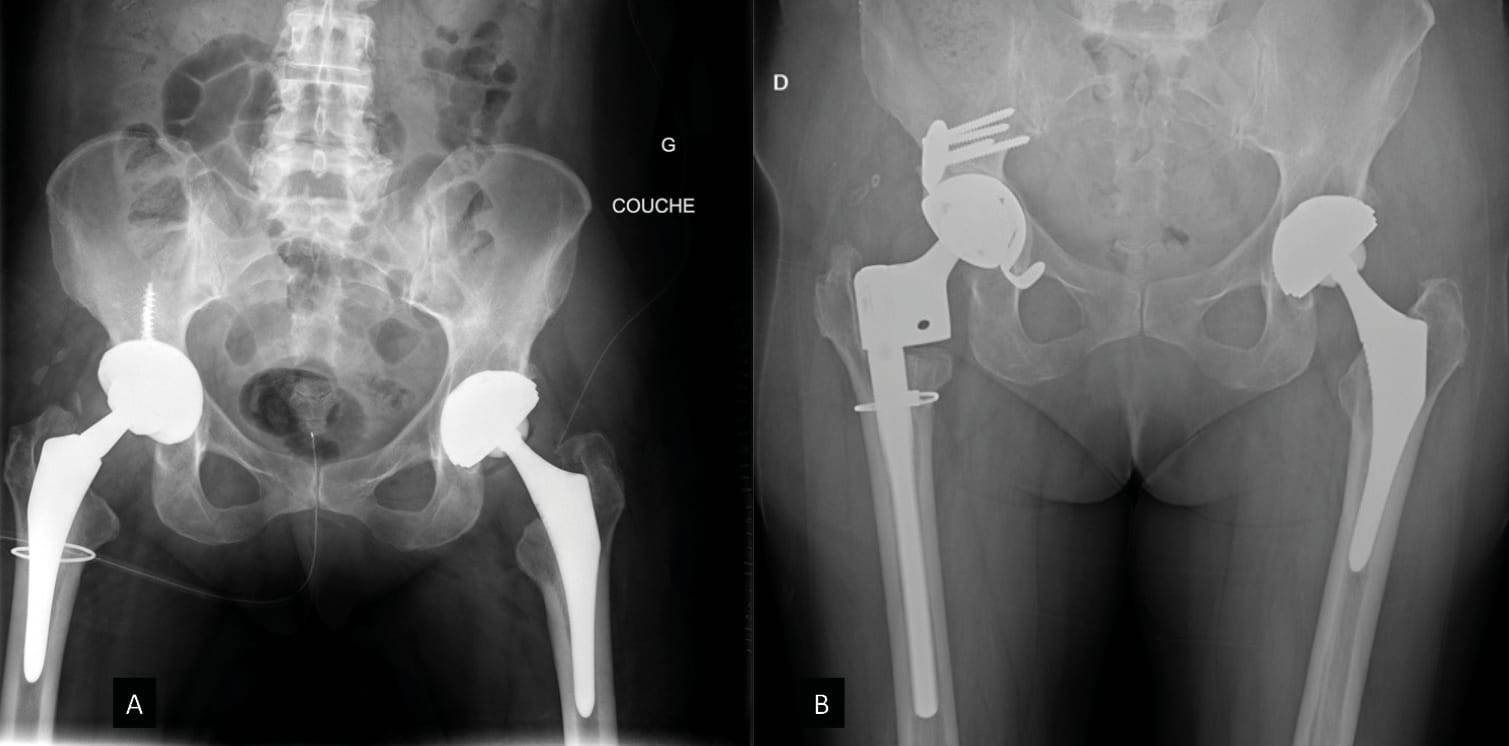

The first option is to use a cementless DM cup either with (Figure 2) or without spikes (Figures 3 and 4) or a peg with a minimum implant size of 40, depending on the manufacturer, and a technically demanding fitting process, resulting in good cup stability for patients with bone defects or poor bone quality, which can, in some cases, leave fewer options. This implant is a first line option indicated particularly in patients with implant instability and moderate bone loss. (Figures 2, 3, 4)

Another option is the modular dual mobility cup. This type of implant remains useful in cases of moderate bone loss and allows the surgeon to optimise the primary fixations (screws) while still taking advantage of the DM concept. The advantages as well as the potential complications specific to this device have been outlined previously [23] Epinette J-A, Coulomb R, Pradel S, Kouyoumdjian P. Do Modular Dual Mobility Cups Offer a Reliable Benefit? Minimum 5-Year Follow-Up of 102 Cups. J Arthroplasty 2022;37:910–6. https://doi.org/10.1016/j.arth.2022.01.025.. We should also point out the risk of liner malseating, although this does not appear to have an impact on the medium term survival curve [50], Bengoa F, Howard LC, Neufeld ME, Garbuz DonaldS. Malseating of Modular Dual Mobility Liners: High Prevalence in Revision Total Hip Arthroplasty. J Arthroplasty 2023:S0883540323003443. https://doi.org/10.1016/j.arth.2023.03.094.[51], Guntin J, Plummer D, Della Valle C, DeBenedetti A, Nam D. Malseating of modular dual mobility liners. Bone Jt Open 2021;2:858–64. https://doi.org/10.1302/2633-1462.210. BJO-2021-0124.R1.[52] Siljander MP, Gausden EB, Wooster BM, Karczewski D, Sierra RJ, Trousdale RT, et al. Liner malseating is rare with two modular dual-mobility designs. Bone Jt J 2022;104-B:598–603. https://doi.org/10.1302/0301-620X.104B5. BJJ-2021-1734.R1. (Figure 6).